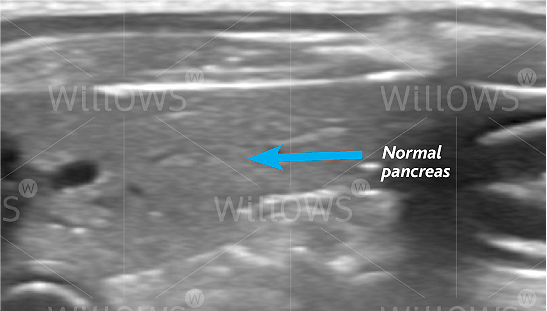

Fig 1: The normal canine pancreas. It is a similar shade of grey to the surrounding fat.

The possibility that a dog may be suffering from pancreatitis is generally suspected on the basis of the history (i.e. loss of appetite, vomiting, etc.) and the finding of abdominal pain on examination by a Vet. Many other diseases can cause these symptoms, as such both blood tests and an ultrasound scan of the abdomen are necessary to rule out other conditions and to reach a diagnosis of pancreatitis. Although routine blood tests can lead to a suspicion of pancreatitis, a specific blood test (called ‘canine pancreatic lipase’) needs to be performed to fully support the diagnosis. An ultrasound scan is very important in making a diagnosis of pancreatitis. In addition, an ultrasound scan can also reveal some potential complications associated with pancreatitis (e.g. blockage of the bile duct from the liver as it runs through the pancreas).